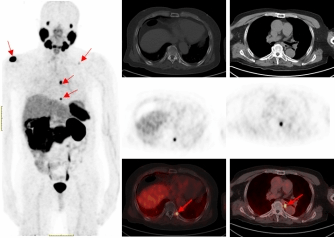

PSMA-PET/CT利用靶向核素分子影像优势,可识别最大直径为4毫米甚至更小的转移淋巴结,68Ga标记的PSMA-PET/CT诊断骨转移灶敏感性更高,能比传统检查手段早一步发现转移灶,为患者的精准治疗赢得时间。

一名75的岁男性患者自2019年确诊前列腺癌后,先后接受过两次内分泌治疗及前列腺癌根治术的综合治疗。在术后两年的复查中发现血PSA持续升高,CT检查和全身骨显像检查均未发现明显异常,医生建议随诊,患者来到污污漫画

附属医院要求进一步检查。经核医学科68Ga-PSMA PET/CT检查后结果显示,双侧肩胛骨、左侧第9后肋、第2腰椎及纵隔淋巴结均已存在癌症转移。

据无锡疾控2023年4月17日发布的最新数据显示,前列腺癌位列男性发病癌种第四位。新诊断的前列腺癌患者中,有一部分在诊断时已发生远处转移,建议有条件的患者做这项检查,特别是中高危的前列腺癌患者。